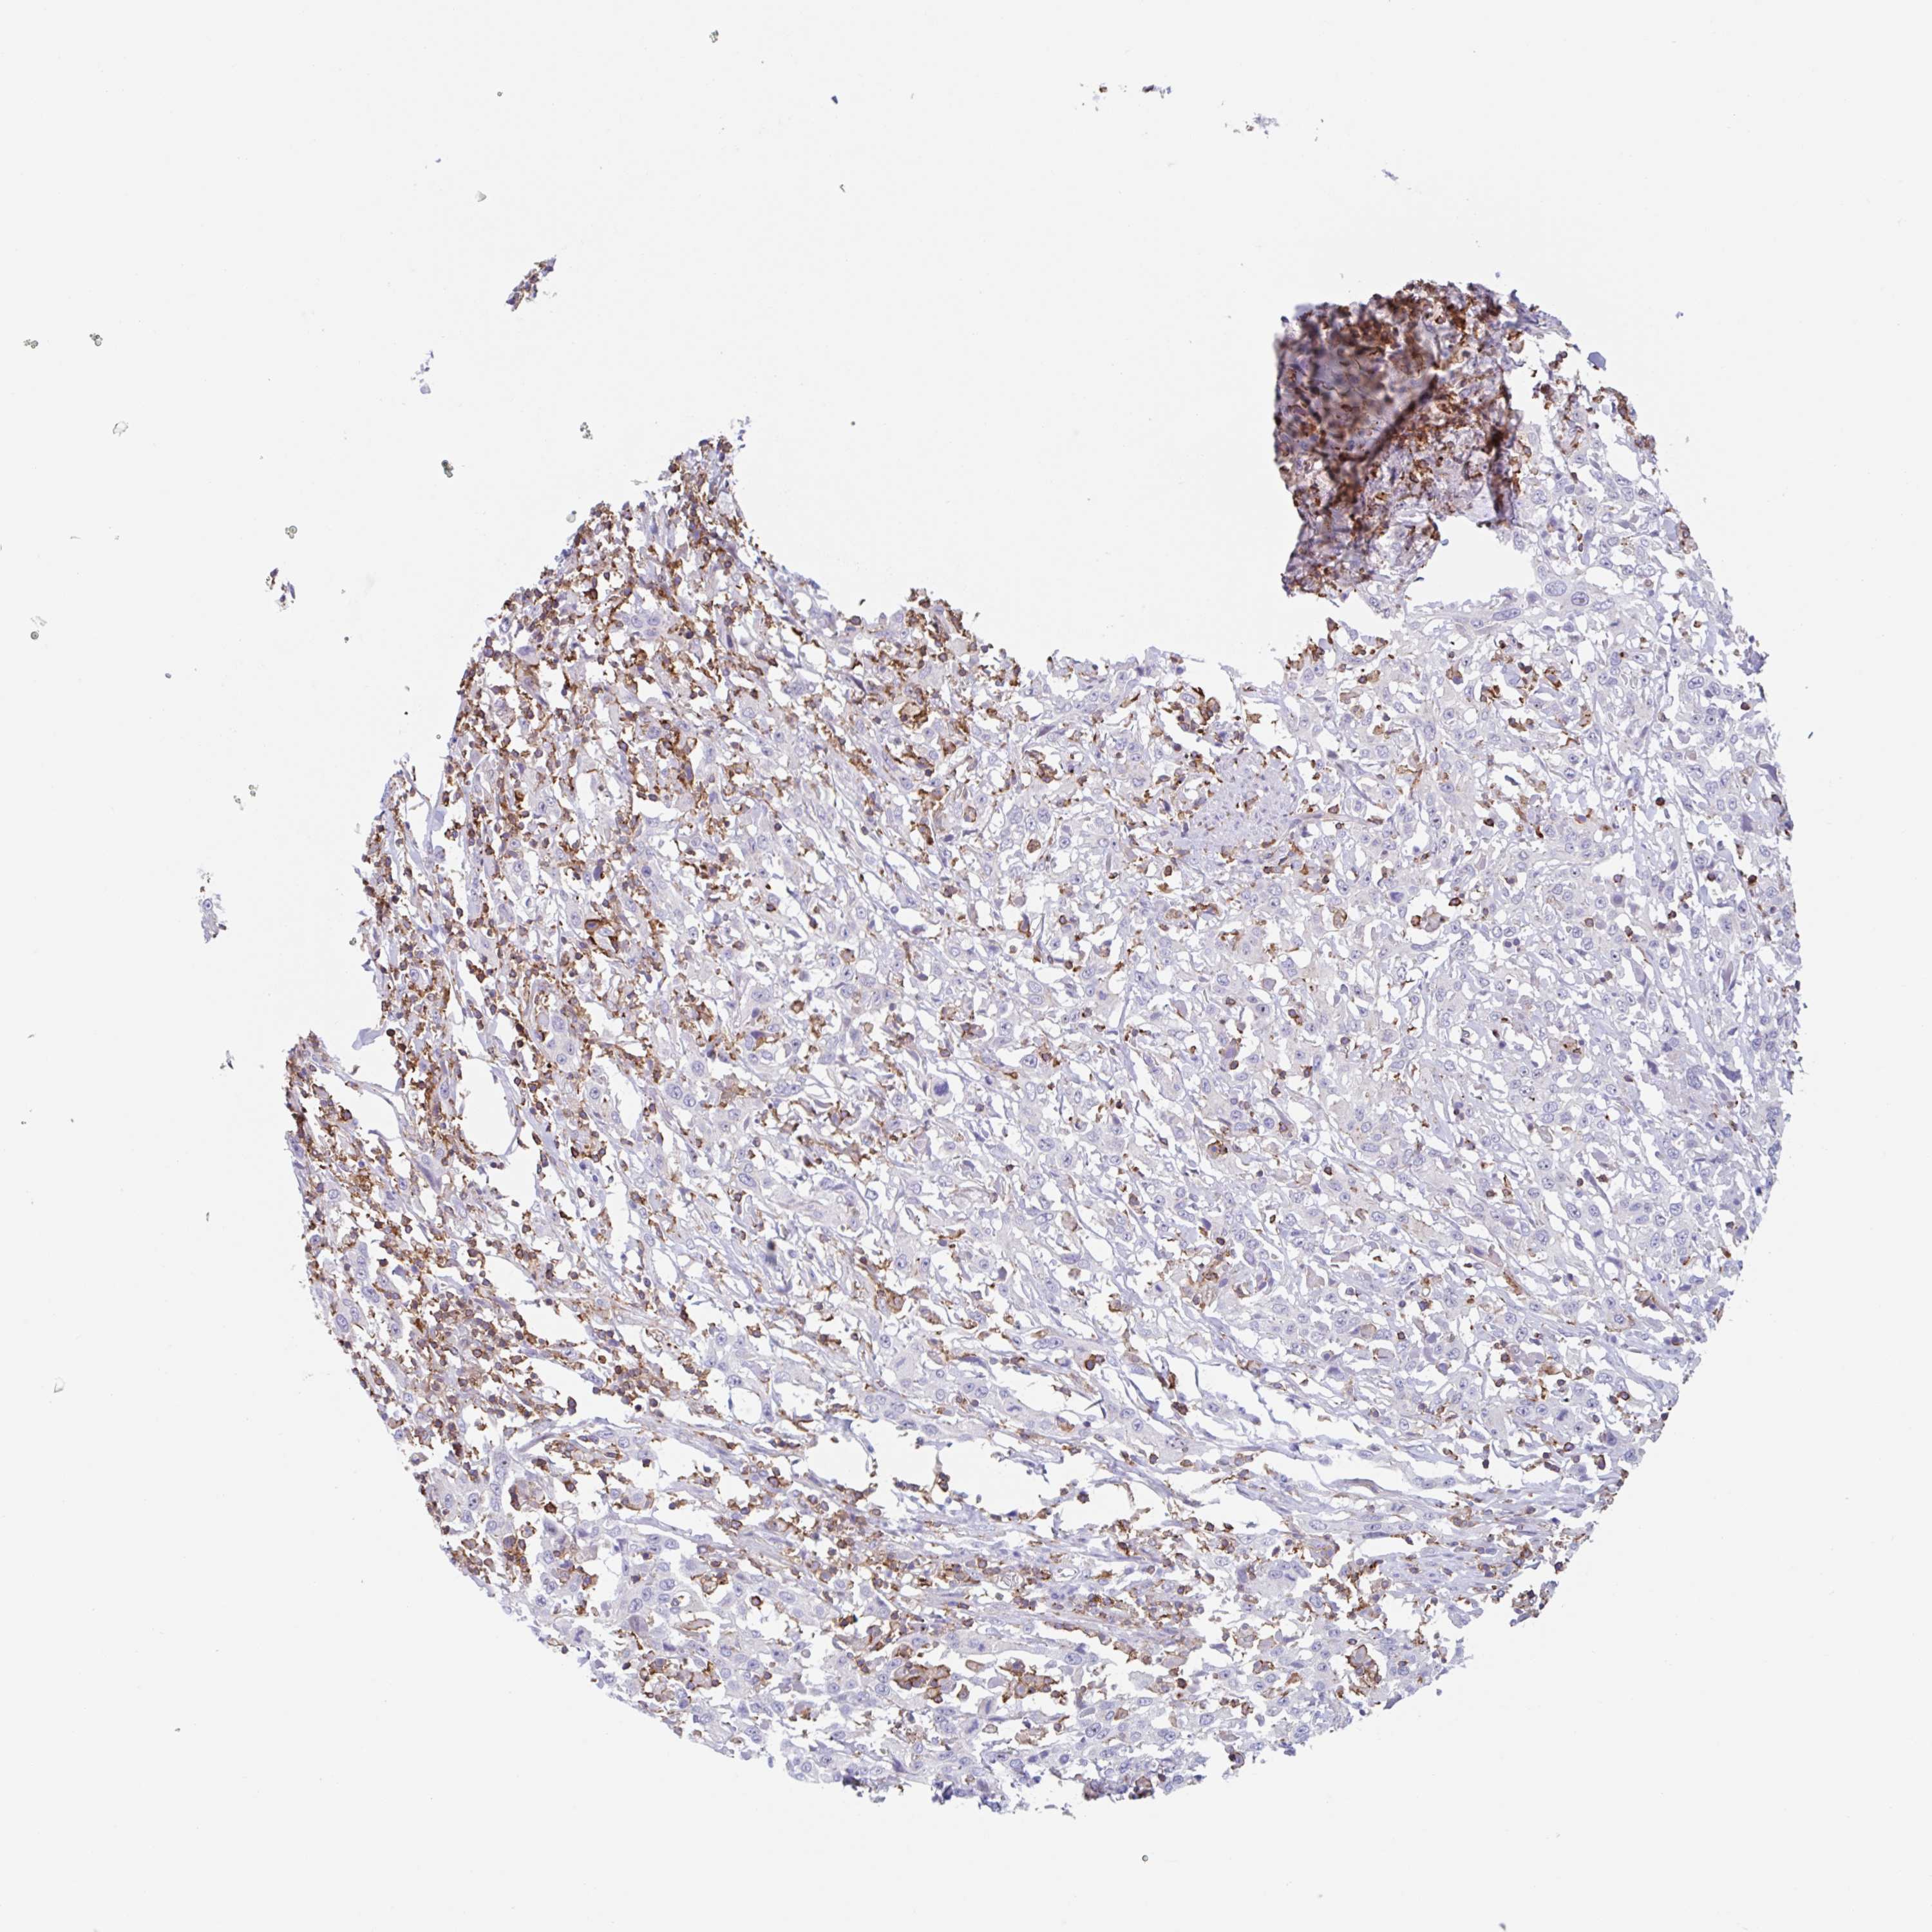

UROTHELIAL CANCER - Protein expressioni

A mouse-over function shows sample information and annotation data. Click on an image to view it in a full screen mode. Samples can be filtered based on level of antibody staining by selecting one or several of the following categories: high, medium, low and not detected. The assay and annotation is described here.

Note that samples used for immunohistochemistry by the Human Protein Atlas do not correspond to samples in the TCGA dataset.

Antibody stainingi

Antibody staining in the annotated cell types in the current human tissue is reported as not detected, low, medium, or high, based on conventional immunohistochemistry profiling in selected tissues. This score is based on the combination of the staining intensity and fraction of stained cells.

Each image is clickable and will lead to virtual microscopy that enables deeper exploration of all samples and also displays staining intensity scores, fraction scores and subcellular localization as well as patient and tissue information for each sample.

Antibody HPA049331

Antibody HPA056959

Urothelial carcinoma, Low grade

Urothelial carcinoma, High grade

Urothelial carcinoma, NOS